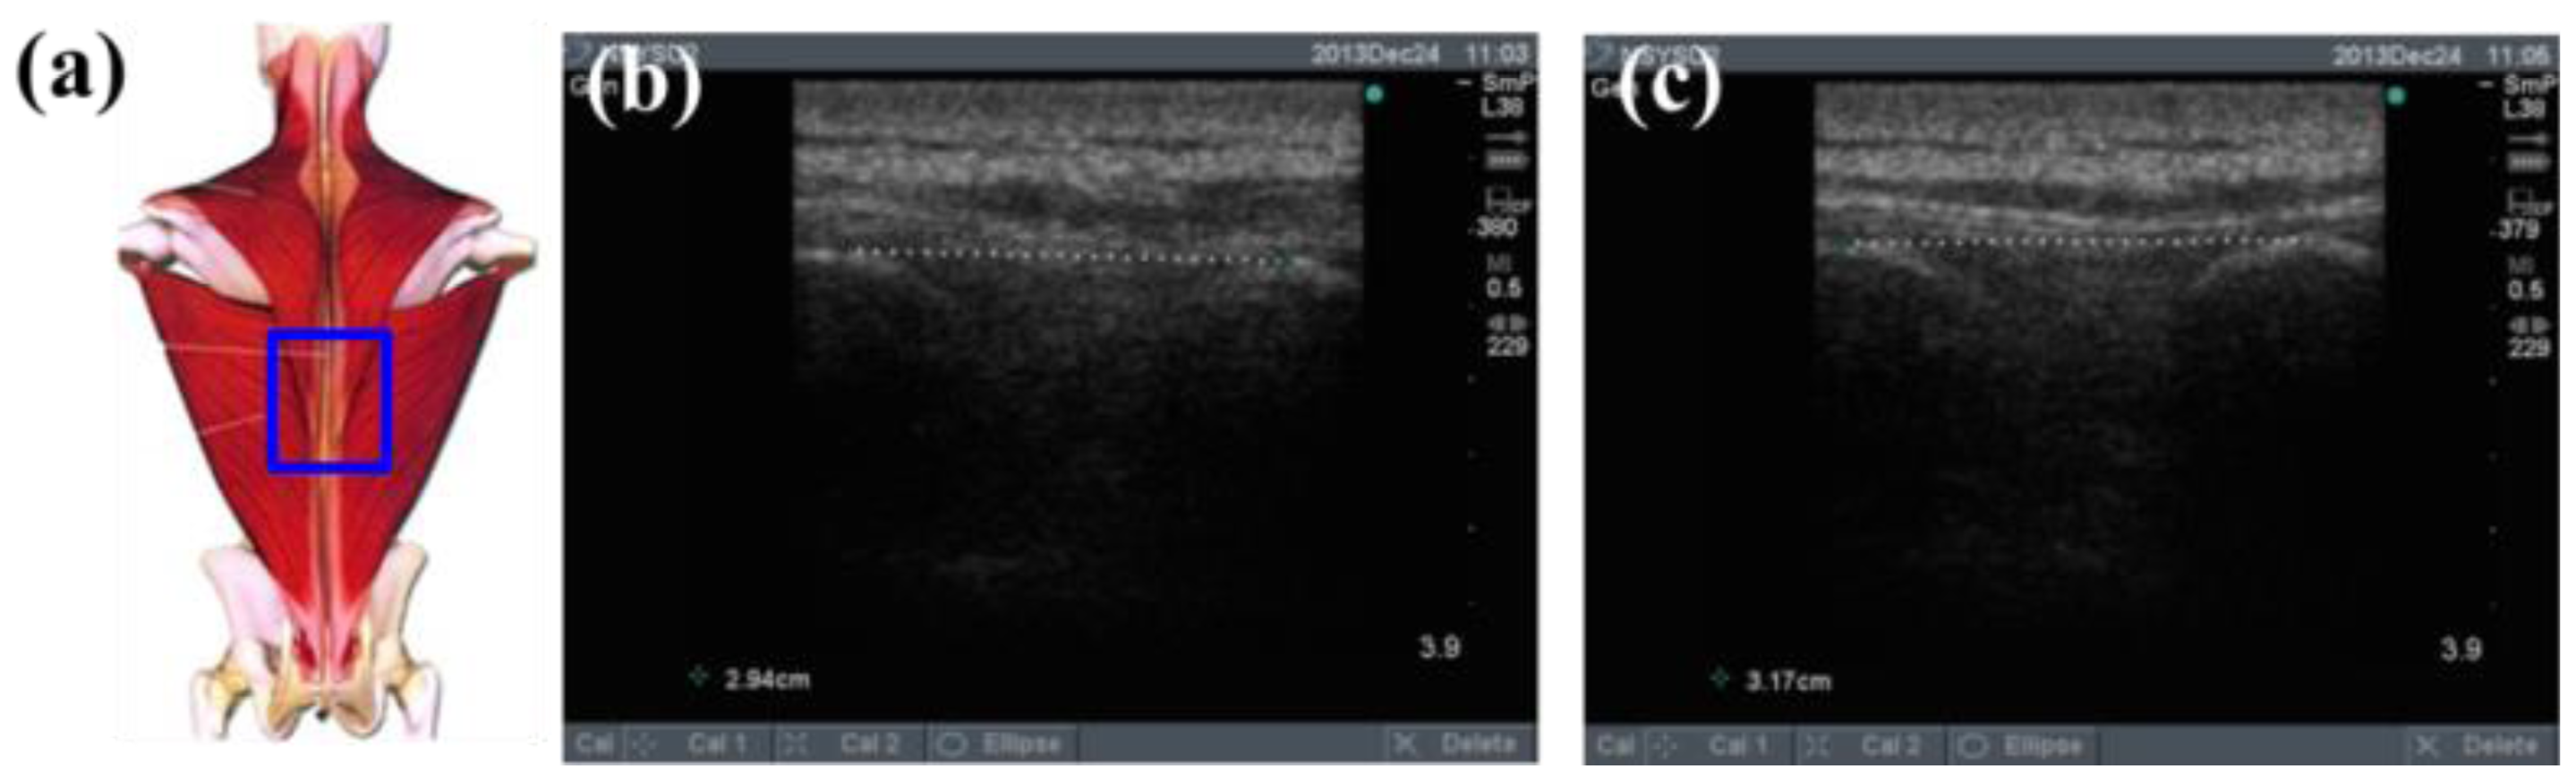

To determine the feasibility of the training system proposed in this study, we used ultrasound imaging to observe the muscles' length changes during contraction and determined whether these changes were correlated with skin stretches. Ultrasound image measurement is used for exploring the human body, such as observing tissue structure, blood or tissue movement, and the mechanical characteristics of tissues. Tissue structure is mainly observed using grayscale images. The primary principle in ultrasound imaging is the reflection of ultrasound waves when the waves encounter different density interfaces in the human body. The piezoelectric crystals in the sensor head receives the signals and converts the signals into images according to the direction, distance, and strength of the waves. Ultrasound imaging is often used to examine tumours, tissues, or organs inside the body. Moreover, ultrasound images are also usually used to exam the muscle and soft tissue in rehabilitation and orthopaedic departments [12–16]. The SonoSite Titan ultrasound system (FUJIFILM SonoSite, Inc, Bothell, WA, USA) was used to measure the muscle length changes during exercise. The trapezius, mid erector spinae, and lower erector spinae were measured. The ultrasound image of the muscles at different trunk angles during Roman chair back hyperextension training is shown in Figures 10, 11 and 12, the (b) component showed the image in the preparatory actions and (c) component showed the image in the flexion 45 degrees. The muscle length in the specific positions is shown in Table 6. The lower erector spinae shown in Table 6 had a muscle shortening length of 0.53 cm (the largest length change). The test position correspond to skin stretch of 20%–35%, as shown in Figure 3b, was the largest change among the three positions. The results showed that during Roman chair back hyperextension training, changes in back skeletal muscle extension length exhibited a positive correlation changes in skin stretch. Therefore, the feasibility of a proof of concept sensor has been demonstrated.

| Trapezius Back Skeletal Muscle Extension Length (cm) | Mid Erector Spinae Extension Length (cm) | Lower Erector Spinae Extension Length (cm) | |

|---|---|---|---|

| Preparatory action | 2.47 | 2.94 | 2.94 |

| Anteflexion | 2.61 | 3.17 | 2.41 |

| Corresponding skin stretch | 0%–3% | 3%–12% | 20%–35% |